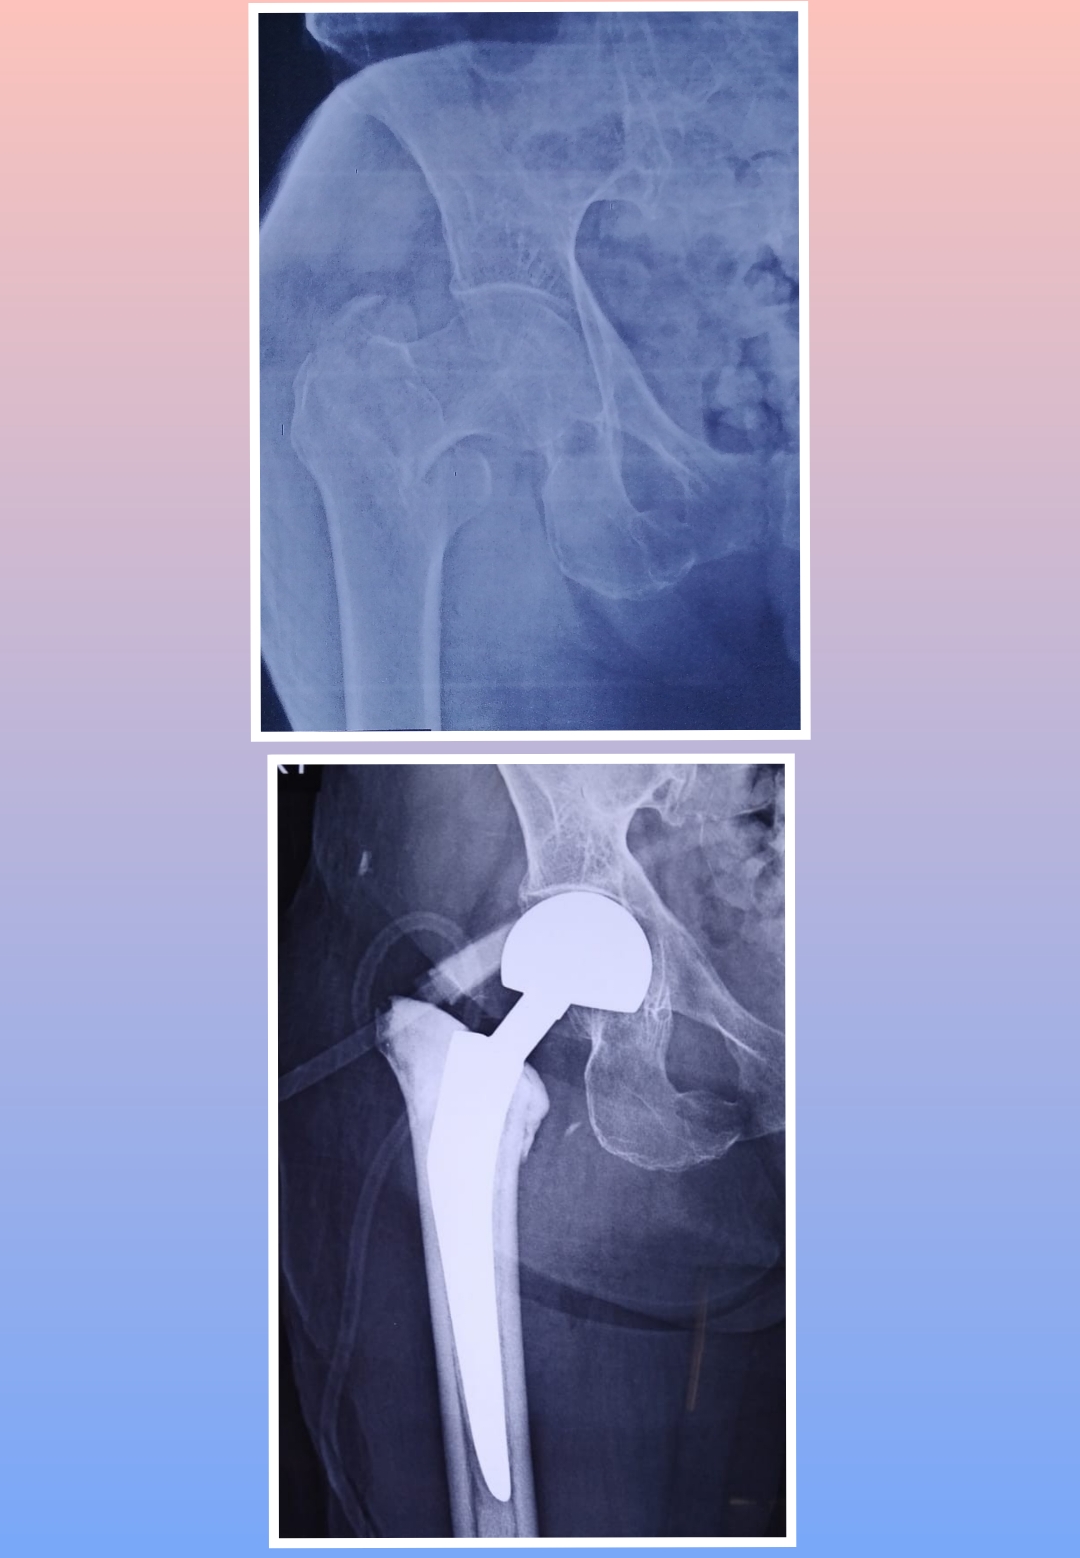

X-ray

Surgeries